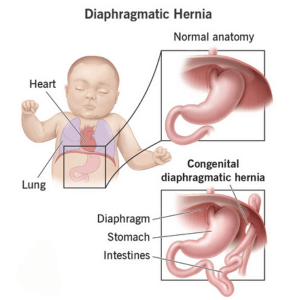

Congenital diaphragmatic hernia (CDH)

Diaphragmatic hernia